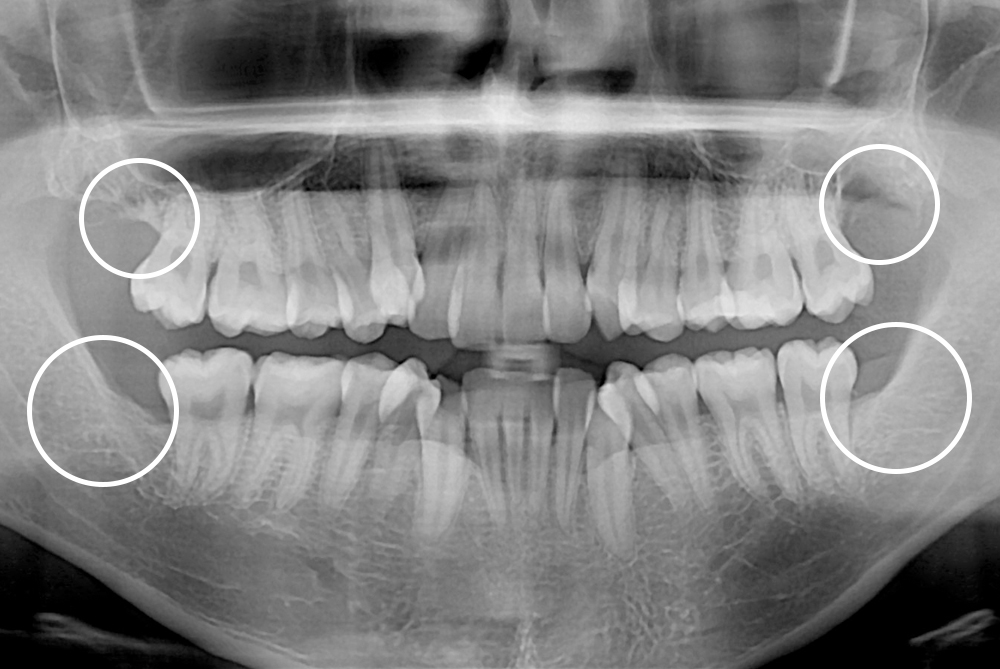

[사랑니] 매복 사랑니 발치

치료후 : 2017-04-11

세종치과는 구강악안면외과학 박사이신 원장님이 발치하는 치과입니다.